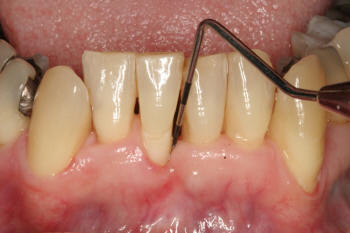

Grado 0 |

Los

dientes y los sitios seleccionados para aplicar

el índice de hemorragia simplificado son los mismos que los tomados en el

índice gingival.